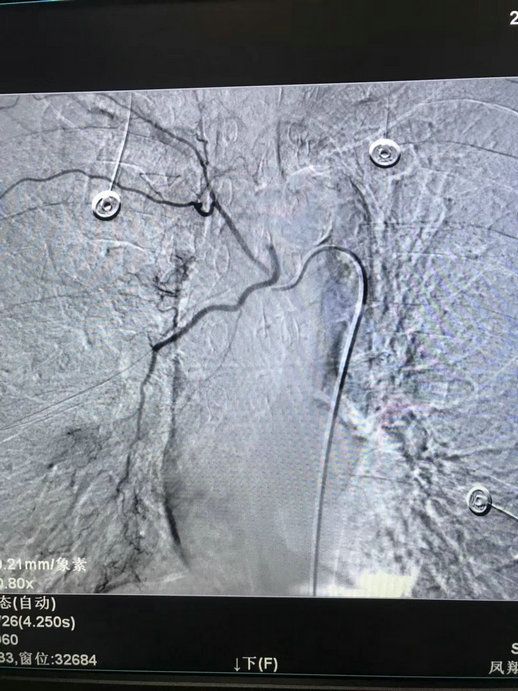

5月15日上午,我院内四科收住了一名反复大咯血的肺癌患者,该患者多次药物治疗后效果不佳,科主任严亚军联系介入科进行急会诊,经与介入科李渊博主治医师反复讨论后,决定急诊行支气管动脉造影+栓塞术。支气管动脉造影显示:右下支气管动脉远端及小分支造影剂弥散。随微导管超选聚乙烯醇栓塞微球+弹簧圈栓塞,再次造影显示:造影剂弥散消失。经术后一周随访,患者再未出现咯血,精神状态良好。